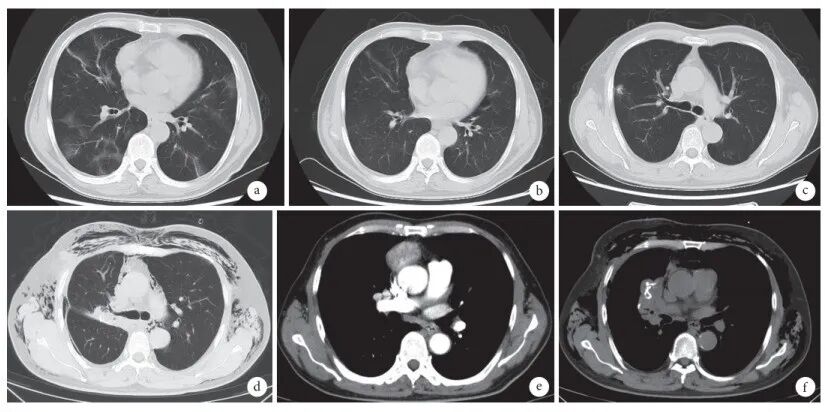

• 胸部CT(图2):双肺多发炎症,考虑病毒性肺炎可能,炎症指数分级Ⅲ级;右肺上叶前段胸膜下混合磨玻璃结节,PNI-RADS Ⅲ级;双肺多发小结节因肺部炎症遮挡显示不清;双肺气肿伴肺大疱;前纵隔肿块,考虑肿瘤性病变。

图片

图2  患者胸部CT检查

注:a. 新冠肺炎治疗前:双肺多发磨玻璃影;b. 新冠肺炎治疗后:病变吸收减少;c. 右肺上叶前段胸膜下不规则结节;d. 肺结节切除术后并发气胸;e. 前纵隔肿块;f. 纵隔肿物切除术后并发气胸。